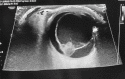

Utility of 2-Deoxy-2-[18F]fluoro-Dglucose positron emission tomography/computed tomography scan in the systemic evaluation of patients with post-COVID-19 endogenous presumed fungal endophthalmitis

Keywords: CT scan; FDG PET/CT; endophthalmitis; mucormycosis.